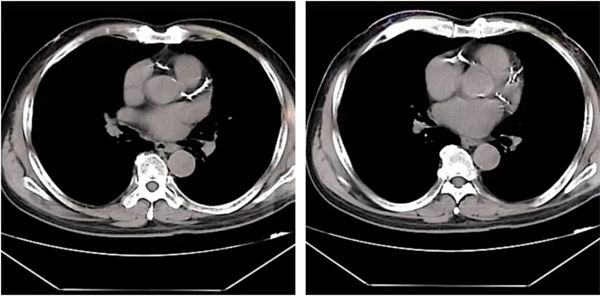

患者術(shù)前造影顯示:RCA全程彌漫性鈣化病變,近-中段狹窄70-90%,遠(yuǎn)段狹窄70%。LM鈣化狹窄50%;LAD近段鈣化狹窄60-70%,D1近段狹窄60%;LCX近段鈣化狹窄50%,遠(yuǎn)段狹窄70%。

術(shù)前造影影像

鄭廣生團(tuán)隊(duì)經(jīng)過對(duì)手術(shù)難點(diǎn)的分析提出了相應(yīng)的手術(shù)策略順利為患者實(shí)施了手術(shù):患者73歲高齡,冠脈多支嚴(yán)重鈣化狹窄,存在左主干病變,右冠重度鈣化,需要主動(dòng)行冠脈旋磨治療,經(jīng)充分處理右冠病變后,于右冠植入支架3枚。術(shù)后患者的胸悶、氣短癥狀明顯緩解,已于近日康復(fù)出院。

術(shù)后右冠造影影像